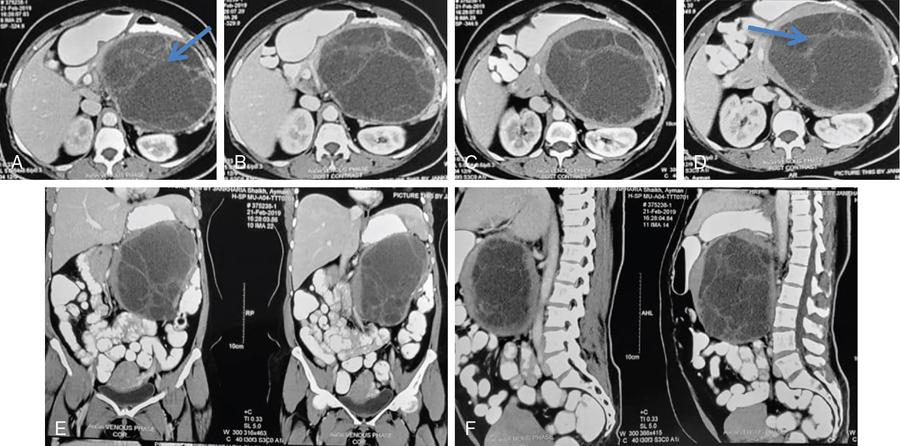

Ritu K. Kashikar, Shrinivas B. Desai, Pooja Punjani Vyas, Nilesh Doctor, Vivek Shetty Advancement and extensive use of imaging in recent times has to lead to increased detection and recognition of cystic pancreatic masses. Imaging however, plays a vital role in noninvasive diagnosis of these lesions, avoiding unnecessary intervention and planning management and follow up guidelines. The aetiology of pancreatic cysts ranges from primary cystic neoplasm to cystic degeneration of solid neoplasm to nonneoplastic cysts (Table 9.19.1). Cystic tumours of the pancreas comprise around 10%–15% of cystic lesions of the pancreas. The aim of this chapter is to educate the reader regarding imaging features of cystic lesions of pancreas, how to differentiate between cysts which can be left alone and those that require further management and also emphasize on latest international guidelines used in stratification of these lesions. Cystic pancreatic lesions are often incidentally detected on USG abdomen performed for other reasons. Although USG is an excellent modality for evaluation of cystic lesions elsewhere, it is unable to adequately characterize pancreatic cysts due to retroperitoneal location of the organ and other confounding factors such as obesity and gases. Most lesions detected on USG require characterization with either MDCT or MRI with MRCP. CEUS improves accuracy in the differentiation between a solid and a cystic lesion and also in determining whether enhancing septa or nodules are present within the cystic lesion. Currently USG also does not have a role in follow up algorithms of pancreatic cystic lesions. Multidetector CT evaluation of pancreatic lesions is best performed with a multiphasic technique (Table 9.19.2). The phases include a precontrast scan, an early arterial angiographic phase, a pancreatic parenchymal phase, and a portal venous phase. The precontrast scan is important for detection of calcification, which may be diagnostic of some lesions. Mucinous cystic neoplasms may be hyperdense on nonenhanced scan suggesting mucin content or haemorrhage. The arterial phase aids in detection of hyperenhancement neovascularity and arterial involvement in pancreatic masses. Optimal parenchymal enhancement of the pancreas is achieved at 35–45 seconds after initiation of injection of contrast agent. This is the pancreatic parenchymal phase. It is in this phase that the tumour pancreas contrast is maximum (Fig. 9.19.1, Table 9.19.3). Most hypoenhancing pancreatic lesions are best detected in this phase. The portal venous phase allows in detection of venous involvement and hepatic metastasis. Delayed phase is typically not required in cystic masses. MDCT has an accuracy of 56%–85% for characterization of cystic pancreatic lesions. MR imaging affords the best noninvasive means for the evaluation of cystic lesions of the pancreas due to superior soft tissue resolution. The helpful distinguishing characteristics of cystic pancreatic lesions, morphology of septae, relation to pancreatic duct are easier to detect at MR imaging and MR cholangiopancreatography (MRCP) than at CT (Table 9.19.4). Studies however indicate that MDCT and MRI are comparable in identifying malignant behaviour of cystic pancreatic lesions. The MRI protocol for evaluation of cystic lesions of pancreas includes T2-weighted single-shot fast spin-echo, T1-weighted in-phase and opposed-phase gradient echo, diffusion-weighted imaging, T2-weighted fat-suppressed fast spin-echo. Three-dimensional T1-weighted fat-suppressed spoiled gradient-echo T2-weighted MRCP. Postcontrast protocol includes dynamic three-dimensional T1-weighted fat-suppressed spoiled gradient-echo (in arterial, pancreatic and portal venous phases) (Fig. 9.19.2, Table 9.19.3). DWI has not found much utility in cystic neoplasms owing to overlap in ADC values. Some studies suggest role in distinguishing malignant from benign tumours in the case of mucinous cystadenoma and IPMN. Secretin is a peptide hormone produced in the intestinal mucosa, which stimulates the secretion of bicarbonate-rich fluid into the pancreatic ducts and transiently increases the tone of the sphincter of Oddi. The increased fluid distention of the pancreatic duct allows better study of ductal anatomy and identifying communication of pancreatic cystic lesions with the pancreatic duct. EUS is excellent in characterization of cystic lesions of pancreas. The proximity between the transducer and the lesions allows precise definition of the structural component of the cysts and components such as small mural nodules are better visualized with EUS than with other modalities. The other advantage of EUS is that cysts fluid aspiration and cytology can be performed. Tumour markers, genetic markers can be evaluated in the aspirated fluid. This allows comprehensive evaluation of cystic lesion. EUS also has therapeutic advantages allowing endoscopic draining of pseudocysts. Recently endoscopic ablation of cysts has been performed. These advantages have led to increasing use of EUS in recent years. This modality is however not indicated in all lesions and imaging should be able to stratify lesions requiring further invasive investigations. Studies have found PET CT comparable to PET alone or CT to determine presence of malignancy in cystic lesions. False positive findings may however be problematic. There is however no consensus for routinely using PET CT in characterization of cystic pancreatic masses. Serum CA19-9 and CEA are routinely done in all pancreatic masses. Though role in cystic lesions is still controversial. Serous cystadenoma is a benign neoplasm composed of glycogen-rich epithelial cells that form innumerable small thin-walled cysts containing serous fluid. It is the prototype microcystic pancreatic neoplasm. They occur frequently in older women (median age, 65 years) and is also called as grandmother lesion. Approximately 40% of pancreatic serous cystadenoma arise from the pancreatic head and uncinate process and 60% arise from the pancreatic body and tail. Serous cystadenomas are usually discovered incidentally at imaging; however, those that are large may cause symptoms. Patients may present with abdominal pain, palpable mass, anorexia, fatigue/malaise, or weight loss. Rarely the patient may present with jaundice. Genetic alterations similar to those in VHL are seen in sporadic SCA and include tumour suppressor gene VHL mutations and overexpression of vascular endothelial growth factor (VEGF). Allelic loss in chromosome 3 have seen in up to 40% cases of sporadic SCA. Serous cystadenomas are variable in size. The size ranges from <0.1 to 25 cm. The tumours are grossly well demarcated from the surrounding parenchyma. The gross appearance of the lesions is variable. It could be microcystic, consisting of innumerable small cysts giving the macroscopic appearance of a sponge or honeycomb. The presence of multiple, microscopic SCN is characteristic of von Hippel–Lindau (VHL). This variety show a centrally located area of fibrotic scar. In Macrocystic/oligocystic variant, borders with the surrounding parenchyma are less defined and the cystic lesion generally does not exhibit a central scar. The Solid variant, the lack of cystic spaces on gross inspection often gives the initial impression of a neuroendocrine or solid pseudopapillary neoplasm. Serous cystadenomas show nonviscous, clear-to-yellow cyst fluid, which provides an important clue to the distinction of SN from mucinous neoplasms. In contrast to intraductal papillary mucinous neoplasm, there is no connection with main or branch pancreatic ducts. These are clinically benign pancreatic epithelial neoplasms exhibiting serous morphology, characterized by a monotonous, cuboidal epithelial cell proliferation with marked cytoplasmic clearing due to intracellular glycogen. The centrally located epithelial cell nuclei are uniformly round to ovoid and not particularly large or hyperchromatic. Abundant diastase-sensitive cytoplasmic glycogen is highlighted by a periodic acid–Schiff stain. These lesions do not show evidence of necrosis, infiltrative architecture, or lymphovascular/perineural invasion, and mitotic figures are generally not observed. A variably prominent pseudocapsule of fibrosis divides parenchyma from the neoplasm On USG the microcystic variant shows lobulated contour with multiple tiny anechoic cysts separated by septae. the central scar containing calcification can be seen if present. Extremely microcystic, honeycomb variant may resemble a solid lesion at conventional US. The macrocystic type, can be mixed type with multiple large (>20 mm) and small cysts, and the unilocular type, which is more difficult to differentiate from mucinous cystadenoma (MCA). Enhancement of the intralesional sepatations is seen on contrast-enhanced USG allowing better characterization of the lesion. The central scar can show homogenous enhancement. Honeycomb variety appears as a hypervascular lesion owing to its extremely microcystic morphology and may resemble solid masses like neuroendocrine tumours. Pancreatic serous cystadenoma can have a varied appearance on CT depending on the morphologic patterns. Serous cystadenomas are typically solitary but may be multiple in von Hippel–Lindau disease, causing an appearance of disseminated involvement (Table 9.19.5). As mentioned previously, the polycystic pattern is the most common appearance of serous cystadenoma. A pattern of a bosselated collection of cysts that usually number more than six is seen. Each cyst may range from a few millimetres to 2 cm in size (Fig. 9.19.5). The other classic CT features include a lobulated contour and presence of a central stellate scar with calcification. This scar is seen in 30% cases and when present is strongly suggestive of the diagnosis. The intralesional fibrous septae show early enhancement after contrast administration. This is a distinguishing feature, as serous cystadenoma is the only hypervascular lesion among the cystic pancreatic neoplasms. Tiny cysts mimicking a honeycomb are the hallmark of this variant and may be poorly depicted as individual cysts on CT. On unenhanced CT, the honeycomb pattern may appear as a well-marginated lesion with soft tissue or mixed attenuation, depending on the size of the cysts and the amount of fibrous tissue. Moderate to strong enhancement is seen in these lesions (Fig. 9.19.6). This appears as a unilocular cyst or it may contain fewer large (>2 cm) cysts. Imaging Features include a lobulated contour, lack of a prominent thickened peripheral wall, and location in the head of the pancreas (Fig. 9.19.7). Owing to its supreme soft tissue resolution, MRI is the modality of choice in diagnosis of serous cystadenomas. The classic MRI features of microcystic variant includes a lobulated lesion with multiple small T2 hyperintense and T1 hypointense cysts with intervening hypointense fibrous sepate. These lesions do not communicate with the pancreatic duct; hence no dilatation is usually seen. Dilatation of pancreatic duct has however been reported in larger lesions. After the administration of gadolinium, the hypervascularization of the central scar and of internal septa may be seen. The morphology of the honeycomb pattern may also be better depicted on MRI. Multiple tiny T2 hyperintense cysts with intervening hypointense septae are seen (Fig. 9.19.8). The oligocystic variant shows fewer larger T2 hyperintense and T1 hypointense cysts and can mimic mucinous cystadenoma. However, the lobulated contour, together with the absence of wall enhancement and a wall thickness less than 2 mm, suggest the correct diagnosis (Fig. 9.19.9) (Table 9.19.6). The differential diagnosis of serous cystadenoma depends on the variety and are listed in Tables 9.19.7 and 9.19.8. Lesions with classic imaging features do not require further investigation or fluid analysis. The fluid in classic cystadenomas is yellow in colour and does not show elevated amylase, mucin or tumour markers. Approximately 20%–50% cases show cytological positivity for periodic acid-Schiff and cytokeratin AE1 and 3. Hemosiderin laden macrophages also do not have high diagnostic accuracy and are seen in only about 43% cases. Current management guidelines suggest (Table 9.19.9). Resection involves distal pancreatectomy or Whipples, depending on location of the tumours and is currently reserved for truly symptomatic cases. Mucinous cystic tumours are a rare subset of cystic neoplasms, constituting approximately 2.5% of pancreatic exocrine tumours. TABLE 9.19.10 The defining and characteristic histopathologic feature of mucinous cystic neoplasms (MCNs) is the presence of ovarian-type stroma similar to that observed in biliary cystadenomas. International Association of Pancreatology recommend that all suspected MCNs be surgically resected. A significant female predilection is seen with approximately 99.7% cases seen in women. As opposed to serous cystadenomas these lesions occur in middle aged women and hence the term mother lesions is used to describe these. The approximate age of occurrence is 50 years with a range from 20–82 years. Mucinous cystic tumours are a dominant cyst that is round or oval and is encapsulated. MCNs may grow slowly over time, at an average rate of 4 mm per year. The most common locations are the pancreatic body and tail (up to 75%). Stromal elements similar to ovarian stroma are the hallmark and key feature that aids in differentiation from IPMN, whose stromal elements are ductal in origin. Tall columnar cells with intracellular mucin arranged in a single row or vertically, forming papillary or polypoidal projections, constitute the epithelial elements. Portions of benign appearing epithelium can be seen adjacent to areas of invasive carcinoma in the same tumour. These lesions show smooth contour on gross appearance with few internal sepate. Peripheral calcification, mural nodule if present suggest malignant cyst (Fig. 9.19.11, Table 9.19.11). Lesions may be asymptomatic in 25% cases. Patients my present with pain in abdomen. Mucinous cystadenoma can also present with pancreatitis. Considering most lesions are located in distal body and tail involvement of splenic vein may lead to left sided portal hypertension. Mucinous cystic tumour is a well-circumscribed cystic mass in the pancreas. Lesions can have an irregular contour to the wall, septations, mural nodularity, and peripheral calcifications. The lesion may however be echogenic due to high by mucin content or haemorrhage which may impair the detection of other features. CEUS may improve detection rate of septa and mural nodules. Lesions are typically well-circumscribed with smooth contour. On unenhanced CT, mucinous cystadenoma may appear hypodense or slightly hyperdense content, due to the presence of variable amount of mucin and haemorrhage. Curvilinear calcifications occur along the periphery of the lesion and are seen in 15% of cases, in contrast study enhancement of the fibrous cyst wall along with enhancement of any septations or mural nodules is seen (Figs. 9.19.12 and 9.19.13).